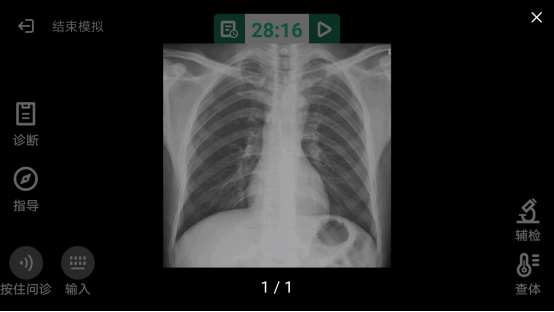

凌晨3点的芝加哥急救中心,19岁的贾斯汀咳出粉红色泡沫痰时,胸片显示他的双肺已成"破碎的棉絮"。这是美国CDC确认的第2879例电子烟相关肺损伤(EVALI)病例,此刻距离他优先次尝试"芒果冰沙"口味烟弹仅过去47天。

第三阶段(15-21天):CT显示弥漫性肺泡损伤

主治医师提供的支气管镜影像显示,患者细支气管内布满金黄色油脂样物质。